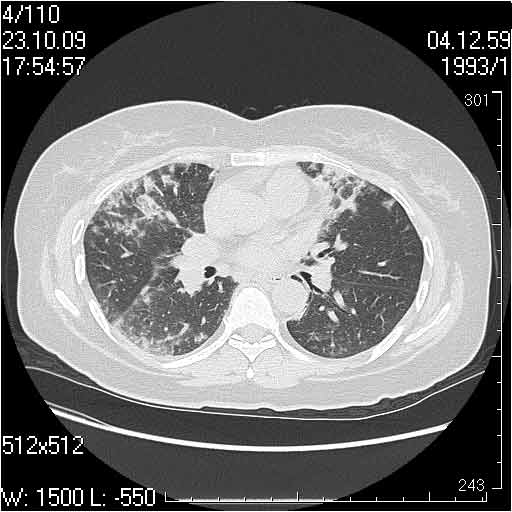

Прошу помочь правильно интерпретировать представленные изображения трех случаев с примерно одинаковой картиной.

Нами они расценены как фиброзирующий альвеолит.

Клиника во всех случаях скудная, незначительная дыхательная недостаточность, субфибрильная температура.

Случай 1: изменения характерны для интерстициальной пневмонии (IIP/UIP idiopathic interstitial pneumonia/usual interstitial pneumonia); говорить о конкретной форме без открытой биопсии затруднительно.

Случай 2: картина патологических изменения довольно типична: GGOs & thickened interlobular septas = "crazy paving" sign. Наличие плотностей по типу матового стекла в сочетании с утолщением междолевых перегородок, даёт признак булыжной мостовой; на первом месте будет стоят диагноз альвеолярных протеиноз.

Случай 3:смешанные изменения; подходят для интерстициальной пневмонии, тактика аналогична случаю 1.